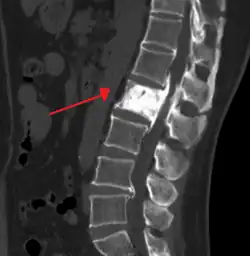

Paget's disease of bone

| Paget's disease of bone | |

| Other names | osteitis deformans, Paget's disease |

![]() | |

| "This 92 year-old male patient presented for assessment of sudden inability to move half his body. An incidental finding was marked thickening of the calvarium. The diploic space is widened and there are ill-defined sclerotic and lucent areas throughout. The cortex is thickened and irregular. The findings probably correspond to the 'cotton wool spots' seen on plain films in the later stages of Paget's disease." | |